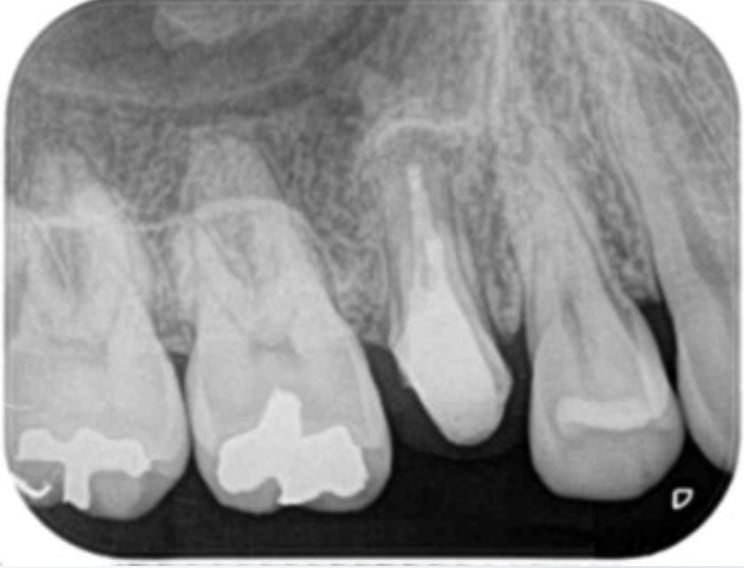

生活歯髄療法(神経を取らないで残す治療)

可能なら神経は取らないで残す方が良いですが、限られた状況でしかできない処置です。

術前(深いむし歯)

術後(神経の一部を切除し特殊な材料で封鎖)

歯髄(歯の神経)の診断は非常に難しく、神経の状態を単純に評価することは不可能です。色々な診査を行い総合的に検討し「神経を残せるか?・残せないか?」を判断して意思決定します。この診査・診断・意思決定のプロセスは専門的な知識や経験が必要なので術者で差が出る部分になります。